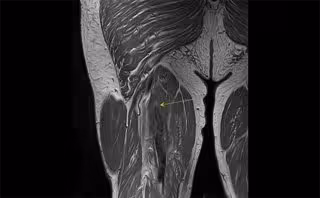

Rotura del músculo semimembranoso con retracción. El músculo toma forma de acordeón indica que ha perdido tensión.

Rotura del músculo semimembranoso con retracción. El músculo toma forma de acordeón indica que ha perdido tensión. - UNIDAD DE RADIOLOGÍA DE CREUBLANCA